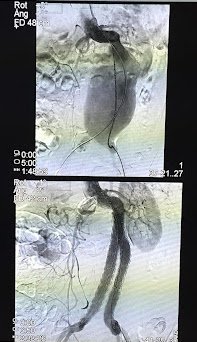

Antes: Oclusión bilateral ilíaca

Antes

Oclusión de ambas venas ilíacas/Sindrome de congestión pélvica

Después: Reconstrucción con stents

Después

Reconstrucción con stents. Flujo normalizado y resolución clínica.